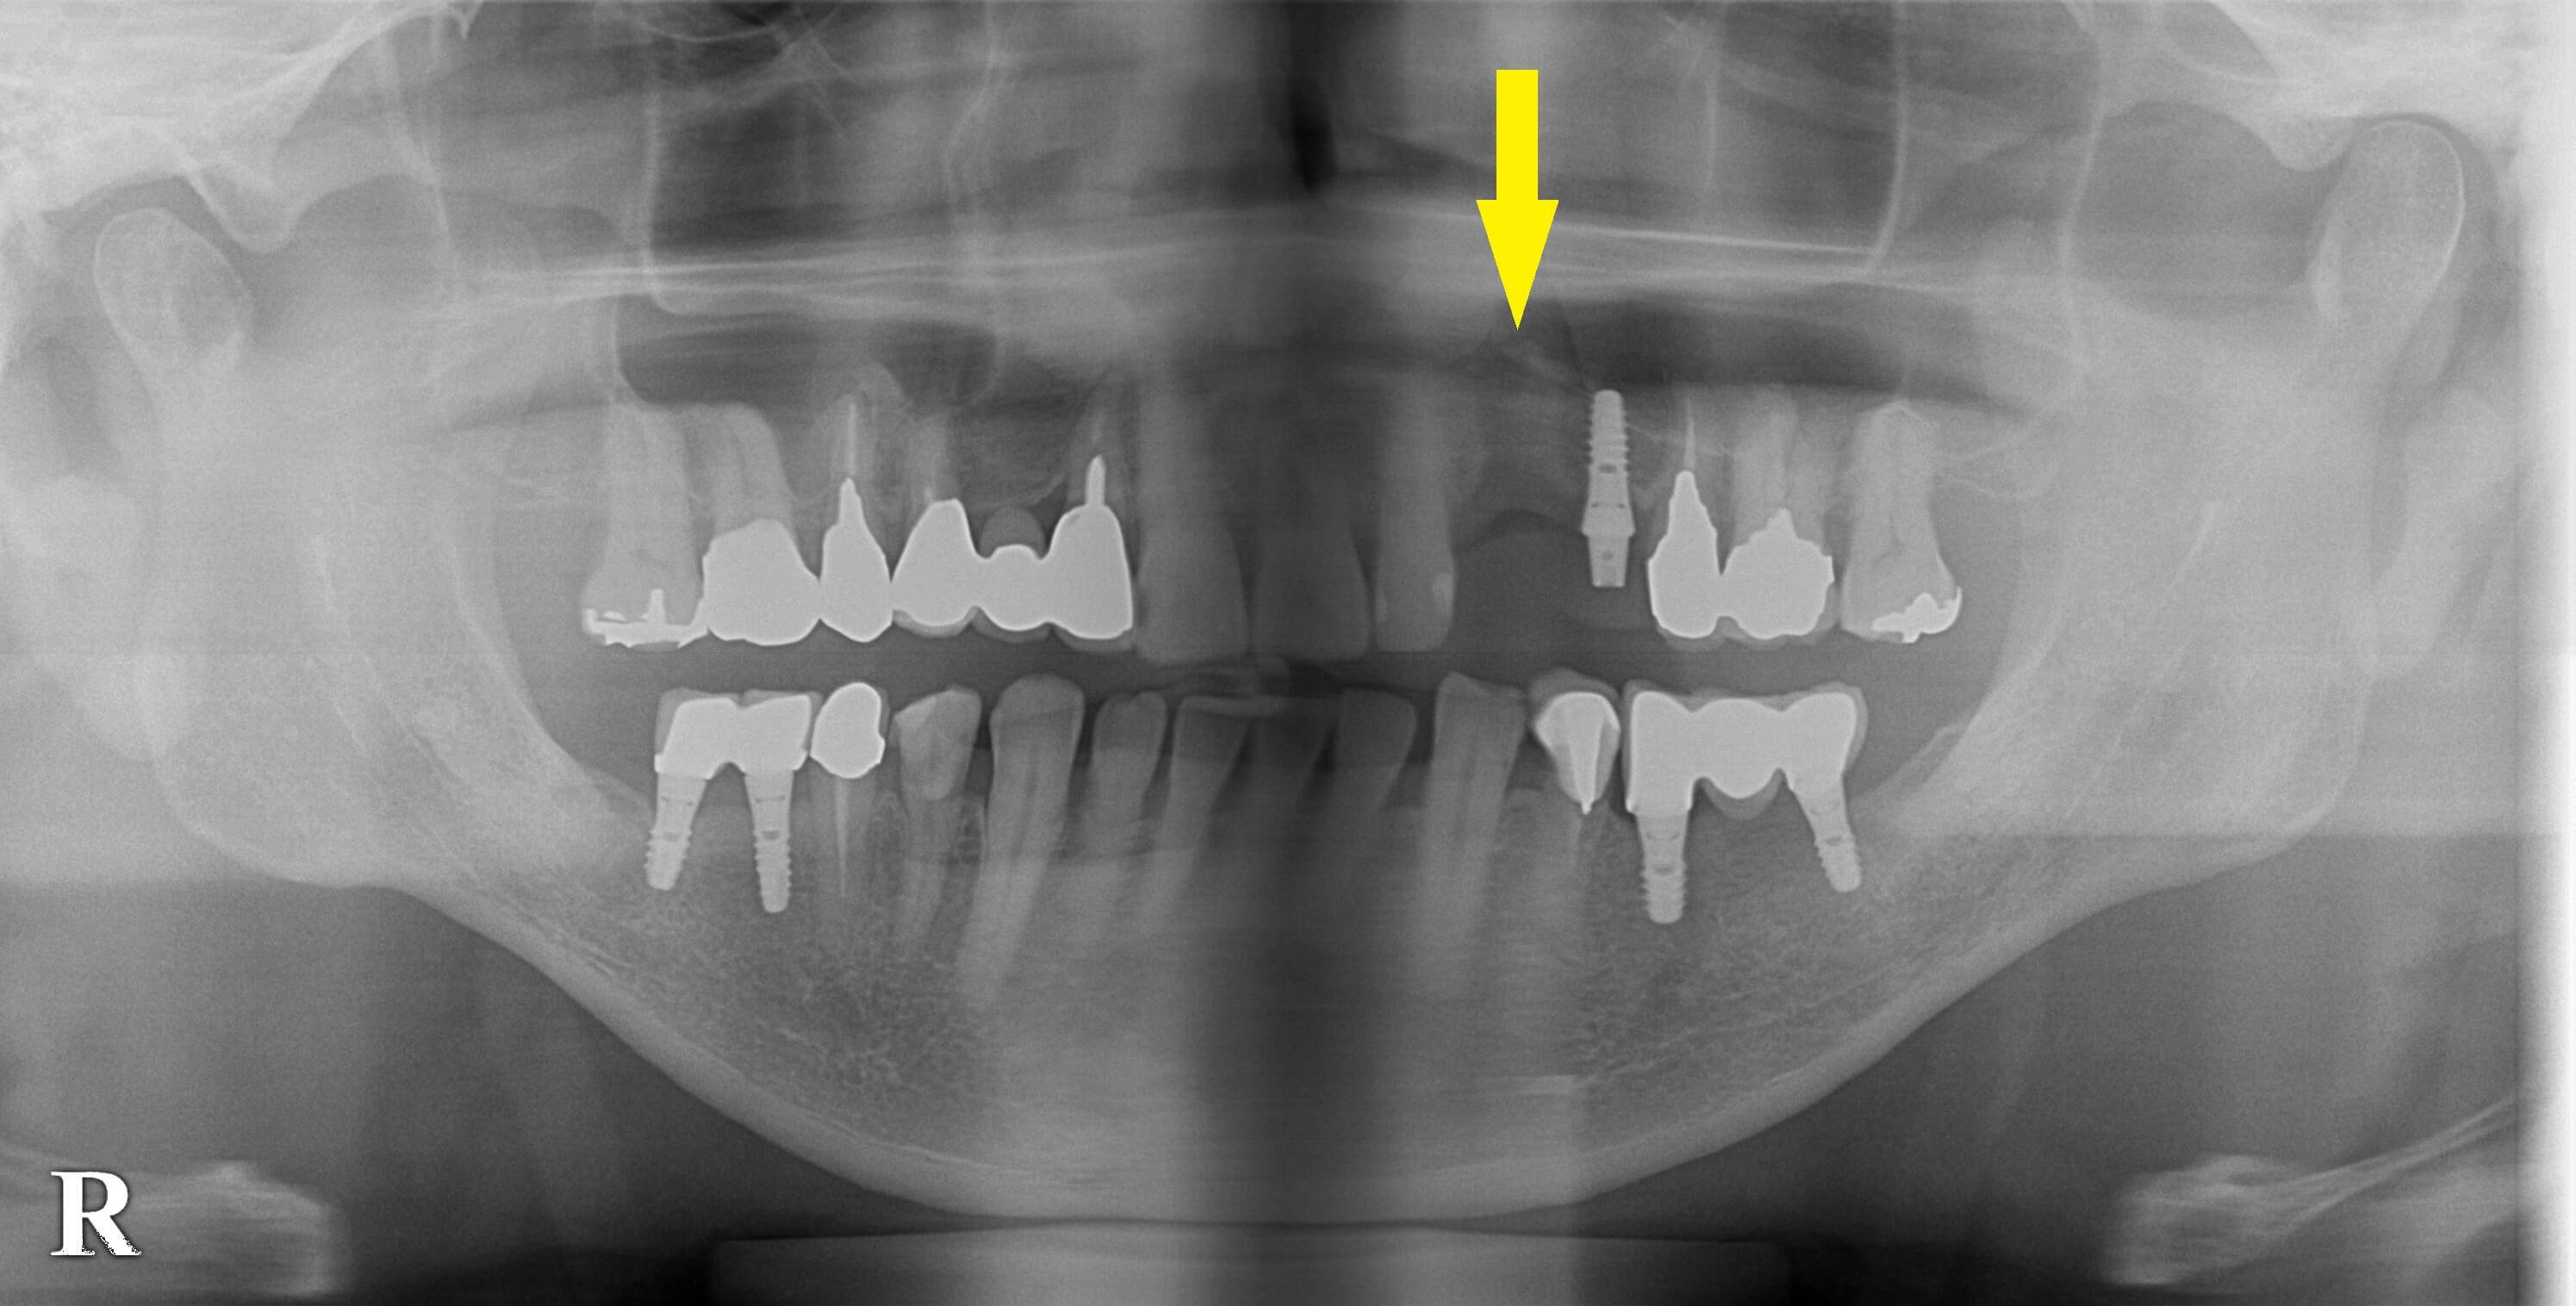

患者様は名古屋在住の60代男性。

すでに数か所のインプラント治療をされている患者様ですが、左上顎犬歯に埋入したインプラントが脱落したそうです。

再度インプラント治療を希望されたのですが、骨が吸収されてしまいインプラントの再埋入が困難と言われたそうです。

CTを撮影してみると、下の2段目の写真左のように、外側の骨がなく薄くなってしまっていました。

ここに骨造成を併用すれば、インプラント埋入が可能であると説明させていただき、本日手術を行いました。

下の2段目の写真右が、術後のCTです。

インプラントが残った骨に埋入、固定され、外側に人工骨が填入されているのが確認できます。